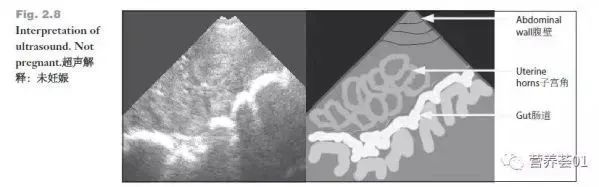

妊娠28天前后。实时超声成像在检查妊娠状态方面是非常有效的(准确率99%)。对于有疑问不太确定的母猪可在配种后35天再检查一次(见图2.8-2.13)。

未妊娠的超声波图像

>